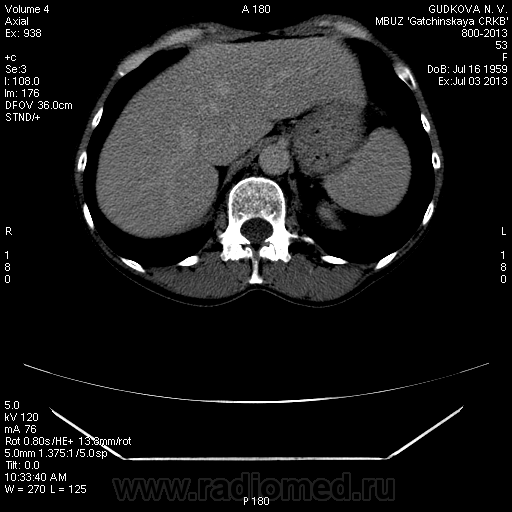

Сегодня, 3.07.13., выполнена МСКТ органов брюшной полости с болюсным контрастированием (омнипак-300 - 100 мл) на программе "3 фазы печени"

На преконтрастной серии - впечатление о расширении нижней полой вены.

В артериальную фазу - интенсивное накопление контраста, как раз в области этого расширения, в 4-5 сегментах печени.Выше и ниже - идет неизмененная НПВ, без контраста (фаза артериальная!) В венозную фазу - небольшая гиперденсная зона перикавально в печени - и все.

Этот участок патологического накопления контраста имеет размер 2,5 * 2,5 см, никак не 1,1 * 1,1(как дают УЗИ-сты)

Это нижняя полая. Заброс контраста в нижнюю полую вену и контрастирование веточек портальной вены в артериальную фазу бывает при неправильной технике проведения болюса. Посмотрите тут: http://www.radiographia.ru/sites/default/files/abdominal_ct_protocols.pdf

Да, это нижняя полая вена.